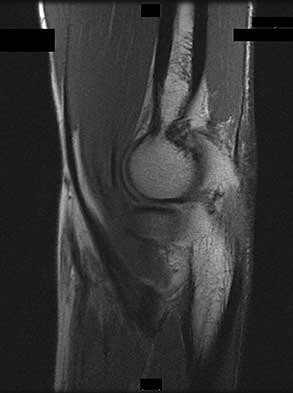

The Gerdy tubercle is located on the anterolateral portion of the proximal tibia and is the insertion for the iliotibial (IT) tract and the origin for fibers of the tibialis anterior muscle. The popliteus muscle originates from the posteromedial aspect of the proximal tibia and inserts into the popliteal groove on the distal lateral femur, deep to and distal to the origin of the fibular collateral ligament. Avulsion fracture of the medial distal femur at the origin of the medial collateral ligament is known as a Stieda fracture and may later develop into a Pelligrini-Stieda lesion. With the knee in extension and the tibia internally rotated, the lateral plateau subluxes anteriorly to the lateral femoral condyle in the anterior cruciate ligament-deficient knee. As the knee is moved from an extended to a flexed position, the IT band switches from being a knee extensor, and, as the forces of the IT band move posterior to the

center of rotation of the lateral femur, the IT band contributes to the posterior reduction of 19

the lateral tibial plateau and the palpable clunk that is felt. The medial collateral ligament is the primary stabilizer when valgus stress is placed on the knee. This is most pronounced when the knee is flexed at 25 to 30 degrees.